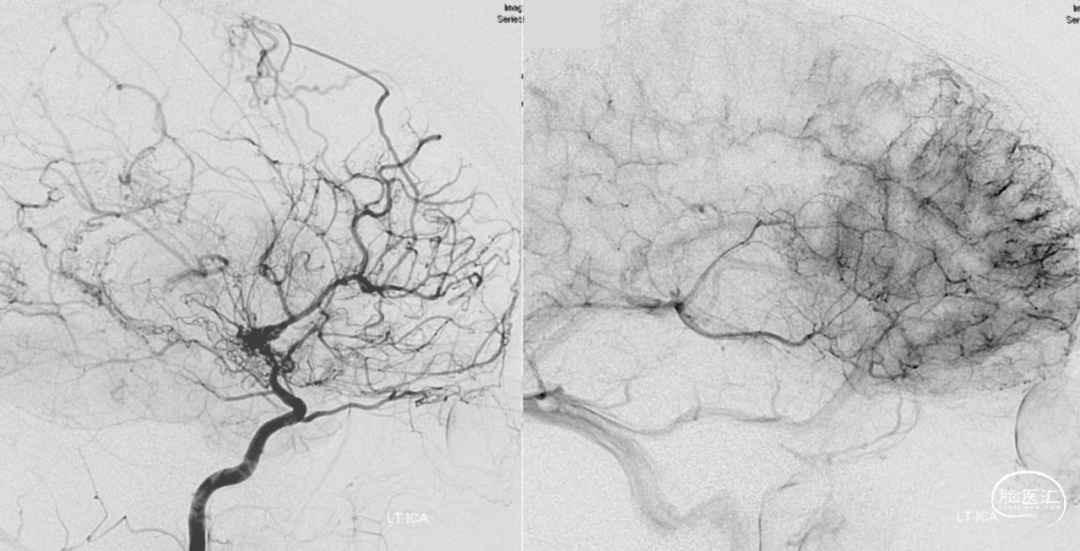

必须对烟雾症患者进行长期的影像学监测,探究有无脑灌注不足、或进行性血管狭窄。

直接的颅内外动脉搭桥嘛,就是直接把颈外动脉的分支和缺血的脑半球里的皮质动脉连起来。间接的血运重建呢,就是拿颈外动脉分支供血的那些组织,转移到缺血的脑半球表面,让它和下面的皮质血管搞个侧支循环,好让缺血区恢复供血。